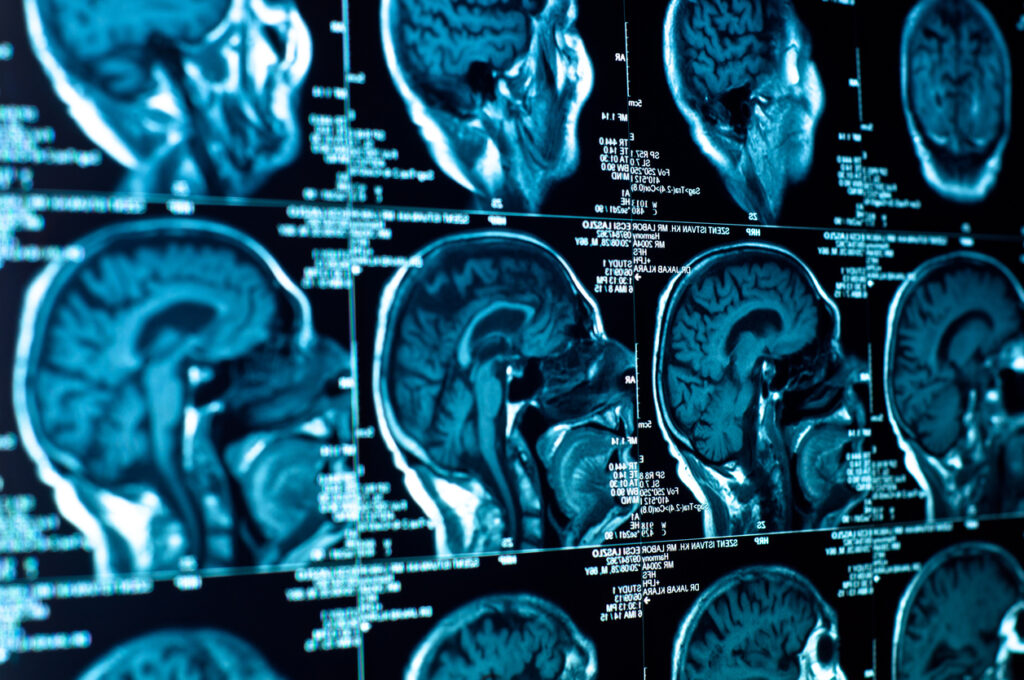

The team explored whether giving temozolomide, as well as performing radiotherapy, would improve the post-treatment outcome for anaplastic astrocytoma patients. These tumour types exhibit similar molecular features to glioblastoma, and there is a high need to understand surrounding optimal treatment.

The researchers selected multiple subgroups of these tumour patients due to the presence of particular mutations in their tumour. This mutation helps to promote genes which protect healthy cells in the brain.